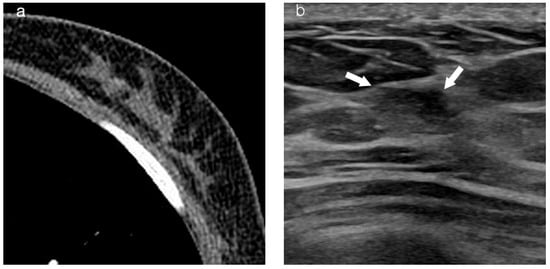

Table 2 summarizes imaging findings based on visibility. On mammography, a mass was observed in 73.8% (31/42) in the visible group, compared to 7.7% (2/26) in the non-visible group (p = 0.000). On MRI, a mass-type presentation was observed in 78.8% (41/52) in the visible group, compared to 38.9% (7/18) in the non-visible group (p = 0.002). Tumor background location on chest CT also significantly differed between the two groups. In the visible group, a fatty background was observed in 67.2% (39/58), compared to a glandular background observed in 16.7% (5/31) in the non-visible group (Figure 1 and Figure 2).

Figure 2.

Images of a patient who underwent left breast-conserving surgery 2 years ago. Recently, DCIS was diagnosed in the conserved ipsilateral breast. (a) Axial contrast-enhanced chest CT did not show an enhancing lesion in both breasts. (b) On US, the mass (arrow) appears as a non-mass-like lesion located in the fibroglandular tissue background of the left breast. (c) MLO view of mammography reveals a grouped suspicious microcalcification (arrow) corresponding to the lesion in the left breast. (d) The 2 min subtracted sequence of MRI shows a non-mass-like enhancing lesion (arrows) corresponding to the lesion in the left breast. DCIS, ductal carcinoma in situ; MRI, magnetic resonance imaging; CT, computed tomography; US, ultrasonography; MLO, mediolateral oblique.